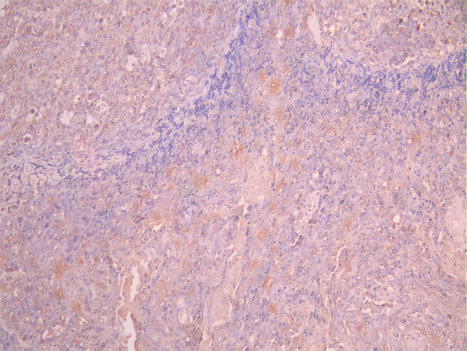

IHC image of CSB-RA957044A0HU diluted at 1:100 and staining in paraffin-embedded human tonsil tissue performed on a Leica BondTM system. After dewaxing and hydration, antigen retrieval was mediated by high pressure in a citrate buffer (pH 6.0). Section was blocked with 10% normal goat serum 30min at RT. Then primary antibody (1% BSA) was incubated at 4°C overnight. The primary is detected by a Goat anti-rabbit polymer IgG labeled by HRP and visualized using 0.05% DAB.

IHC image of CSB-RA957044A0HU diluted at 1:100 and staining in paraffin-embedded human cervical cancer performed on a Leica BondTM system. After dewaxing and hydration, antigen retrieval was mediated by high pressure in a citrate buffer (pH 6.0). Section was blocked with 10% normal goat serum 30min at RT. Then primary antibody (1% BSA) was incubated at 4°C overnight. The primary is detected by a Goat anti-rabbit polymer IgG labeled by HRP and visualized using 0.05% DAB.